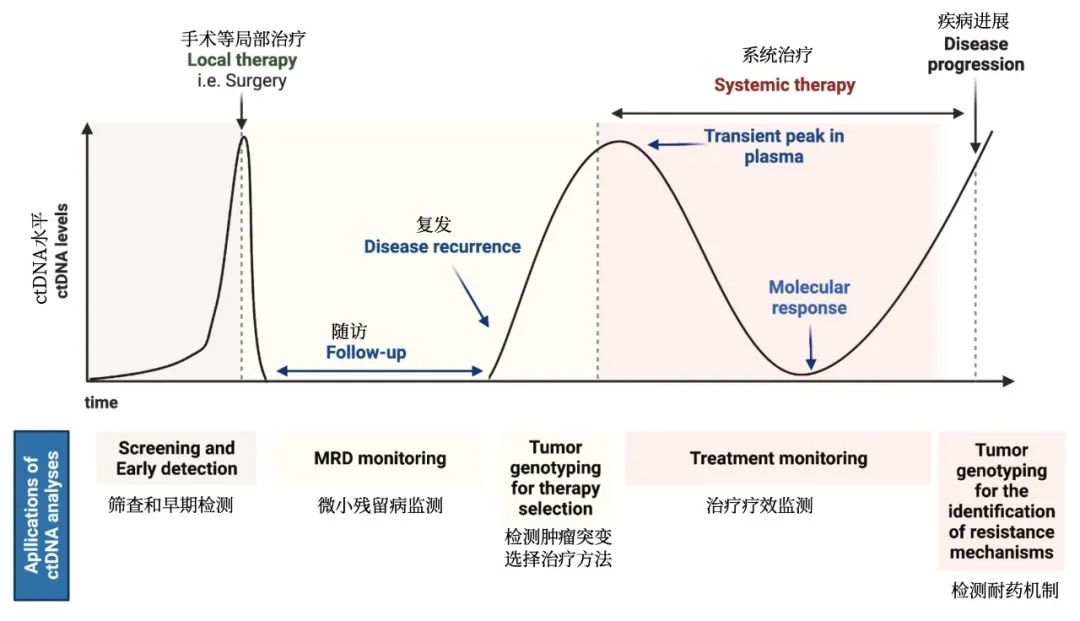

何志勇主任介绍,经过再次对肿瘤活检和检验检测,发现李先生仍然存在EGFR突变的肿瘤克隆。

何医生介绍,三代EGFR-TKI伏美替尼由于化学结构上的优化,具备提高药物浓度而不增加副反应的可能,国内外有相似的研究报道。因此,建议李先生开始口服“双倍剂量伏美替尼”靶向治疗。令人欣喜的是,1个月后复查,李先生肺部及肝脏转移灶较前明显退缩,疗效评价达到部分缓解。

目前,李先生仍在口服“双倍剂量伏美替尼”治疗,肿瘤控制良好,已经维持稳定近一年,且并未有副作用,目前患者生活质量良好。

近年来,何志勇主任团队在双倍剂量伏美替尼治疗三代EGFR-TKI耐药的临床实践中,做了临床层面的探索,并总结了临床经验。近2年来,团队共应用双倍剂量伏美替尼18例,其中,3例是初治脑转移患者,15例是三代EGFR-TKI耐药且经历多线治疗后的患者,治疗都能达到不同程度的肿瘤缩小,总体缓解率为86%(13/15),中位疾病缓解时间为4个月,最长的超过17个月。

另据介绍,三代EGFR-TKI耐药后肺癌患者的治疗,是目前临床上的难点和热点。近年来,何志勇主任团队致力于在临床中探索不同的行之有效的策略。除了双倍剂量伏美替尼,团队还采用节拍治疗克服三代EGFR-TKI耐药,总结了28例患者的临床数据,疾病控制率达到89.3%